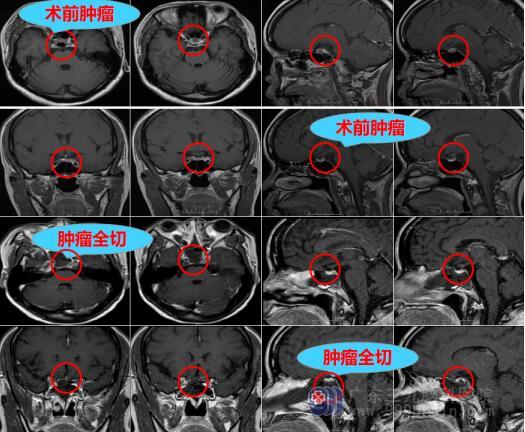

因为怀疑是脑肿瘤,曾女士多方打听后来到脑专科医院——广东三九脑科医院,在神经外十科住院治疗。神经外十科欧阳辉教授和邓心情主治医生给曾女士安排了细致、全面的检查,头颅MR确认“脑垂体瘤”。

欧阳辉教授团队对曾女士的病情进行全面分析,根据曾女士的病情可以进行手术治疗。手术选择神经内镜辅助经鼻蝶脑垂体瘤切除,该手术方式采用非常细微的器械,从鼻子进行手术,既能切除肿瘤,又不留下任何刀口。

曾女士的手术非常顺利,手术后1天即可下病床活动,复查脑MRI示垂体瘤完全切除,3天后顺利出院。